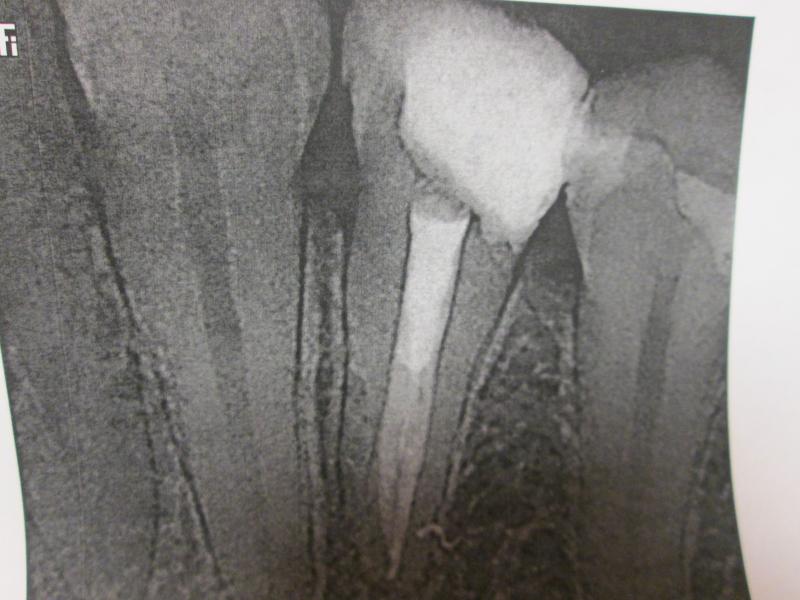

DR JET LOVES ROOT CANALS

General Dentist,  Performs Root Canals ONLY - Microscope Trained Dentist

"DR. JET'S MISSION IS TO PERFORM  ROOT CANALS FOR A REDUCED FEE USING THE LATEST TECHNOLOGY  AND TECHNIQUES TO SERVICE THE MANY PEOPLE WHO ARE UNINSURED OR UNDER-INSURED GIVING EVERYONE AN OPPORTUNITY TO SAVE THEIR TOOTH!"